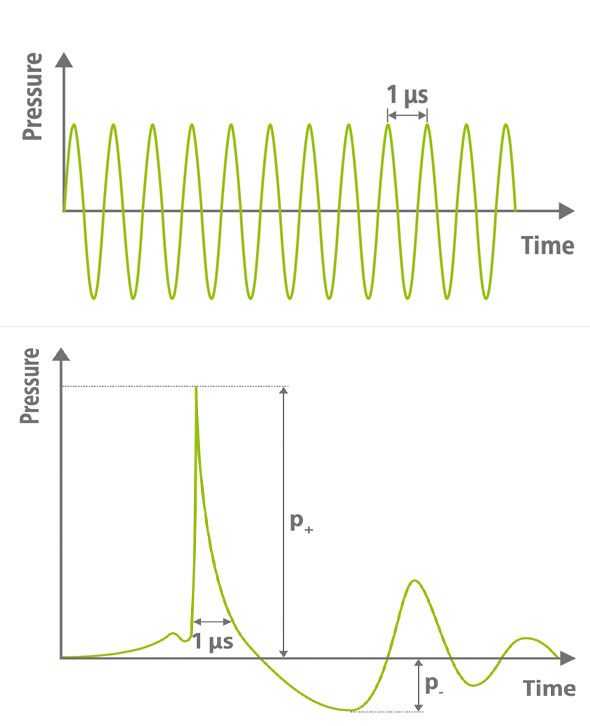

Shock waves and ultrasounds

Both shock and ultrasonic waves are acoustic waves that occur in a similar frequency range. Nevertheless, they differ significantly from each other. While a continuous wave with numerous oscillations characterizes ultrasound, a shock wave is characterized by a single shock pulse followed by a stretching wave with a smaller amplitude. In addition, due to the fluctuating high-frequency exposure, the energy of the ultrasound waves is absorbed by the tissue and can heat it - an effect that is not observed with shock waves. Thus, TPS stimulation does not cause tissue overheating.